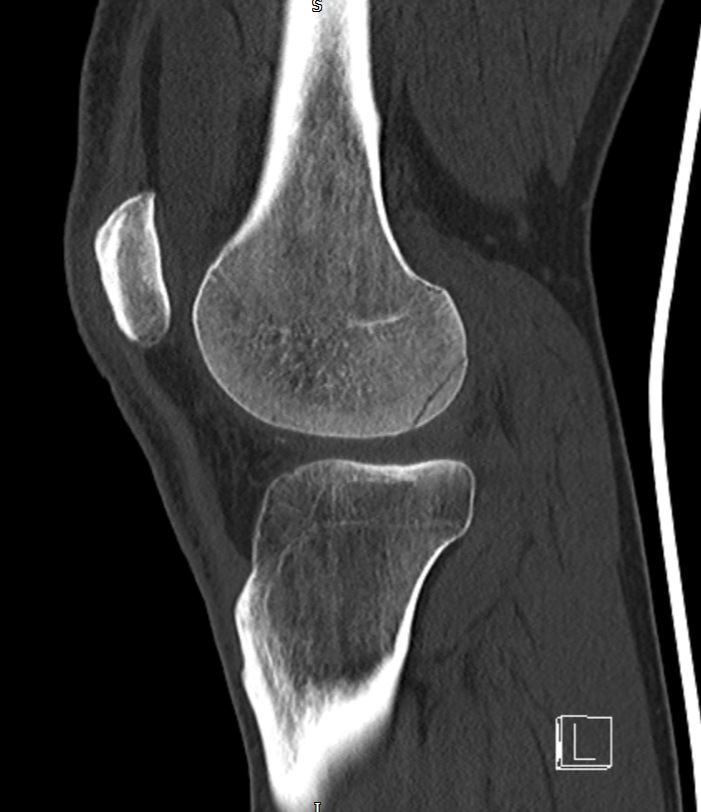

Computed tomography (CT) scan showed an OCF of the posterolateral femoral condyle (Figure 3 & 4). The MRI scan further confirmed the presence of an OCF of the lateral femoral condyle, and injury to the Medial Patellofemoral Ligament (MPFL), the latter is a secondary restraint to patella dislocation (Figure 5 & 6).

Figure 3 Sagittal CT Scan Left Knee.